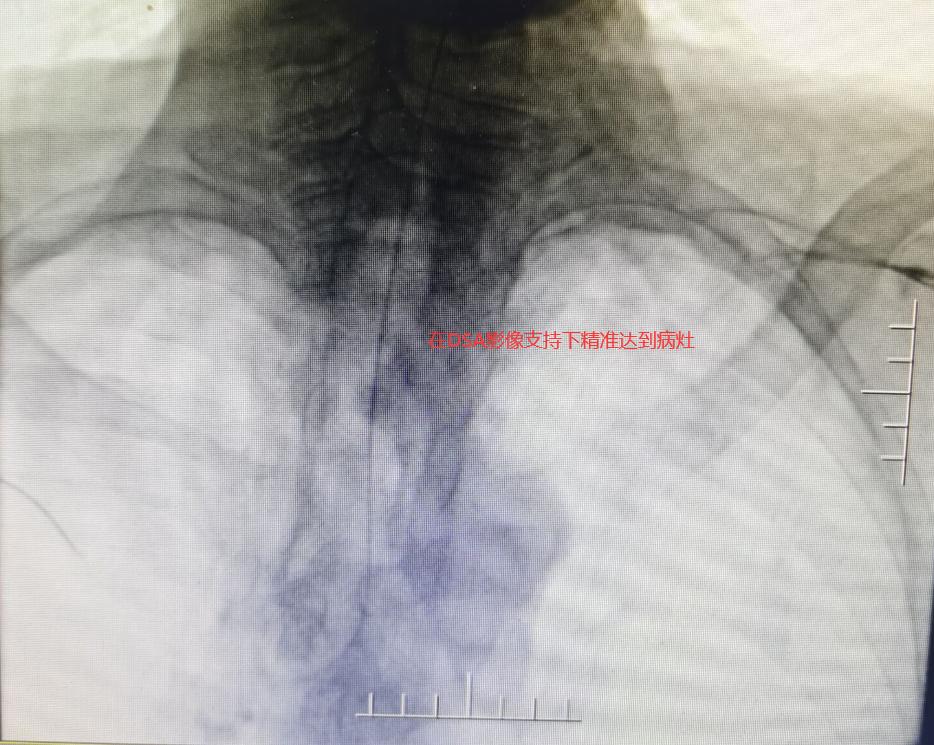

住入肿瘤介入科后,检查发现患者为食管癌致食管气管瘘,患者已无法正常进食,出现气短、咳嗽、咳痰等症状,且因食管气管瘘口的存在,进食食物入肺部导致肺内感染。经肿瘤介入科团队会诊及与患者家属再三沟通后,决定给予患者“食管堵瘘”治疗,在做好充分准备后,介入科团队在DSA引导下行气管支气管支架置入术,术后造影提示瘘口得到有效封堵。患者生命及生活质量明显提高。

在DSA影像支持下精准直达病灶